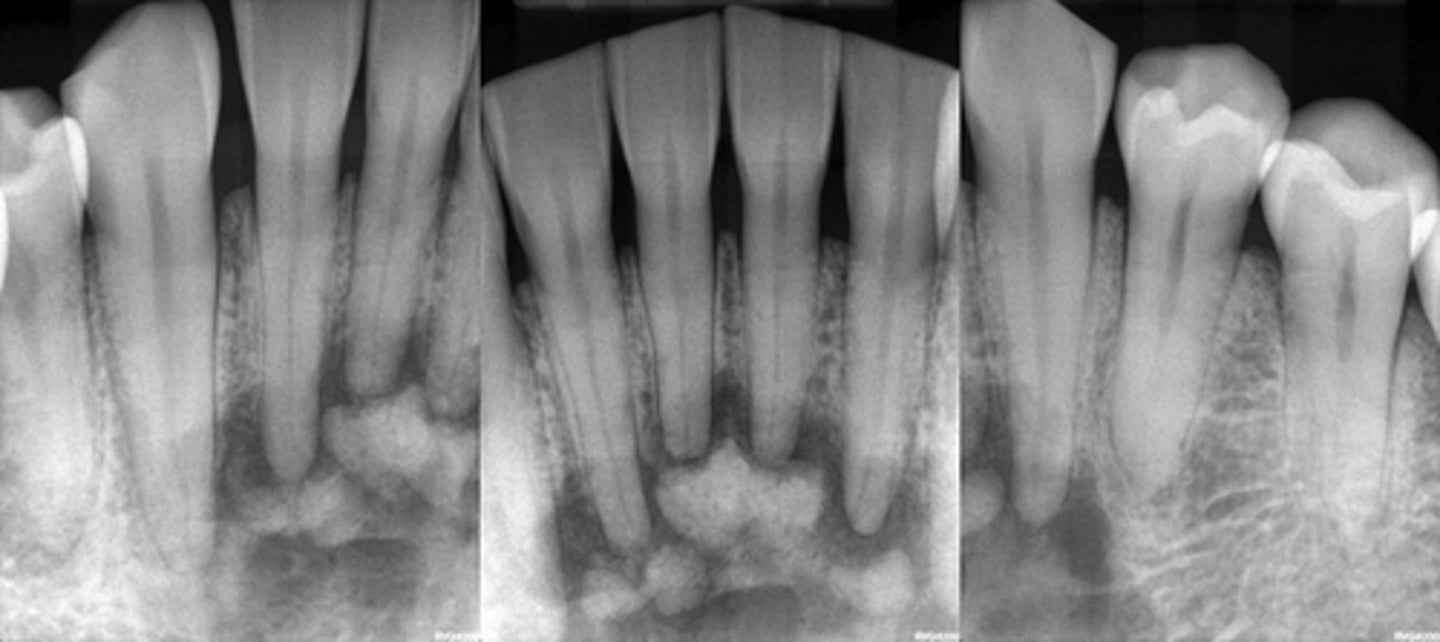

PCOD - Developing- Mature stage

PCOD- Mature stage

PCOD through its stages from Early ---> developing ---> Mature